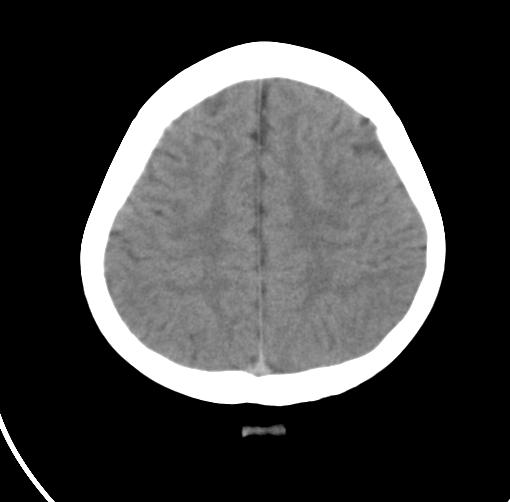

以下是引用sunjh2266在2007-7-31 23:35:00的发言:[br]脉络膜裂,是胚胎发育过程中脉络襞突入侧脑室下角构成脉络丛时形成,位于丘脑下部与海马之间,走行与海马平行。脉络裂内侧通于环池,外侧为侧脑室下角,前面是海马钩及杏仁体,后部与海马沟交通。脉络裂内有参与组成侧脑室脉络丛的脉络膜前动脉及脉络膜后外动脉及其分支走行。[br] mri轴位像,在大脑脚的前外侧多能显示脉络裂的前部,呈左右走行的含脑脊液间隙,前后内外分别与杏仁体、海马、海马钩及侧脑室下角相邻(图1);冠状位像,在扫及脑干的多个层面上,脉络裂均可被清晰显示,因而是显示脉络裂的最佳扫描方式。偏前的部分层面还可见到呈切迹状的海马沟走行于海马旁回内上方;矢状位像,海马旁回上方可见一分叉状裂隙,类似一斜卧的“入”字,接近水平走行的一撇为脉络裂,而由后上向前下走行的一捺为从扣带沟延续而来的海马沟。[br] [br]